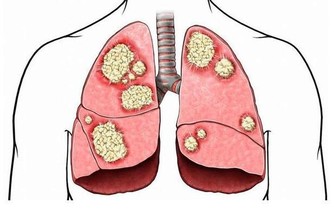

當患者未能及時接受治療時,癌細胞會擴散到身體的其他組織和器官,例如肝臟。

而當癌細胞進一步擴散,病情逐漸惡化時,會影響到消化系統以外的部分。

例如患者的糞便會參有血跡,體重也異常減輕,時常感到疲倦乏力,由於胃部有積液還會引起胃脹胃痛;

嚴重時還會導致貧血和呼吸困難,皮膚和眼白也會開始泛黃。